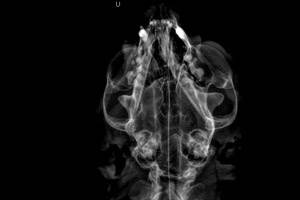

- Рентгенограмма челюсти. Используется для подтверждения перелома нижней челюсти и может показать вывих

височно-нижнечелюстных суставов. Поскольку большинство переломов нижней челюсти являются болезненными, то для проведения рентгенографии может потребоваться анестезия. На основании расположения и тяжести перелома, а также сведений, полученных из общения с владельцем животного, можно сделать выводы о методах лечения, прогнозе и расходах.